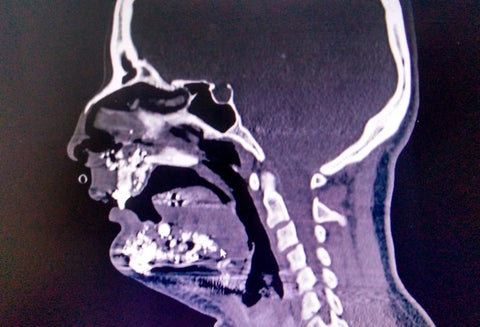

Los daños que sufrió la mujer

Los daños que sufrió la mujer Crédito: Imagen suministrada a LA FM y RCN Radio